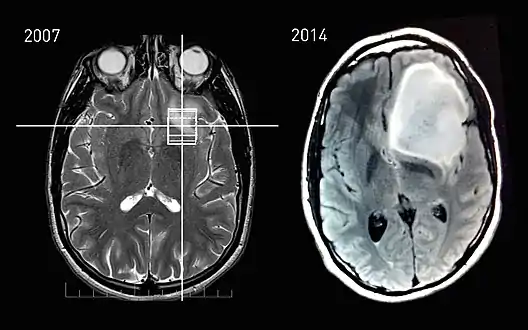

MRI scans of a patient with astrocytoma, showing the tumor's progression between the incidental finding in 2007 and the onset of phenotypical changes in 2014.

Tumor progression is the third and last phase in tumor development.[1] This phase is characterised by increased growth speed and invasiveness of the tumor cells. As a result of the progression, phenotypical changes occur and the tumor becomes more aggressive and acquires greater malignant potential. Together with the progression, more and more aneuploidy occurs. This may be evident as nuclear polymorphism.